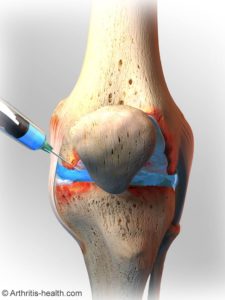

- Injections

Steroid injections or viscosupplementation injections can be used to diminish inflammation and provide long-term pain relief. Injections are offered at your doctor’s office and are typically well tolerated for pain relief. Steroids usually provide up to three to six months for relief, and the newer viscosupplementation shots can last up to a year.

Image courtesy of arthritis-health.com

Some specialists are experimenting with stem cell aspirates and even platelet-rich plasma injections to battle arthritis pain. Since the source of these injections come from the patient in the form of marrow aspirates or peripheral blood draws, they are considered natural alternatives to traditional medical choices.